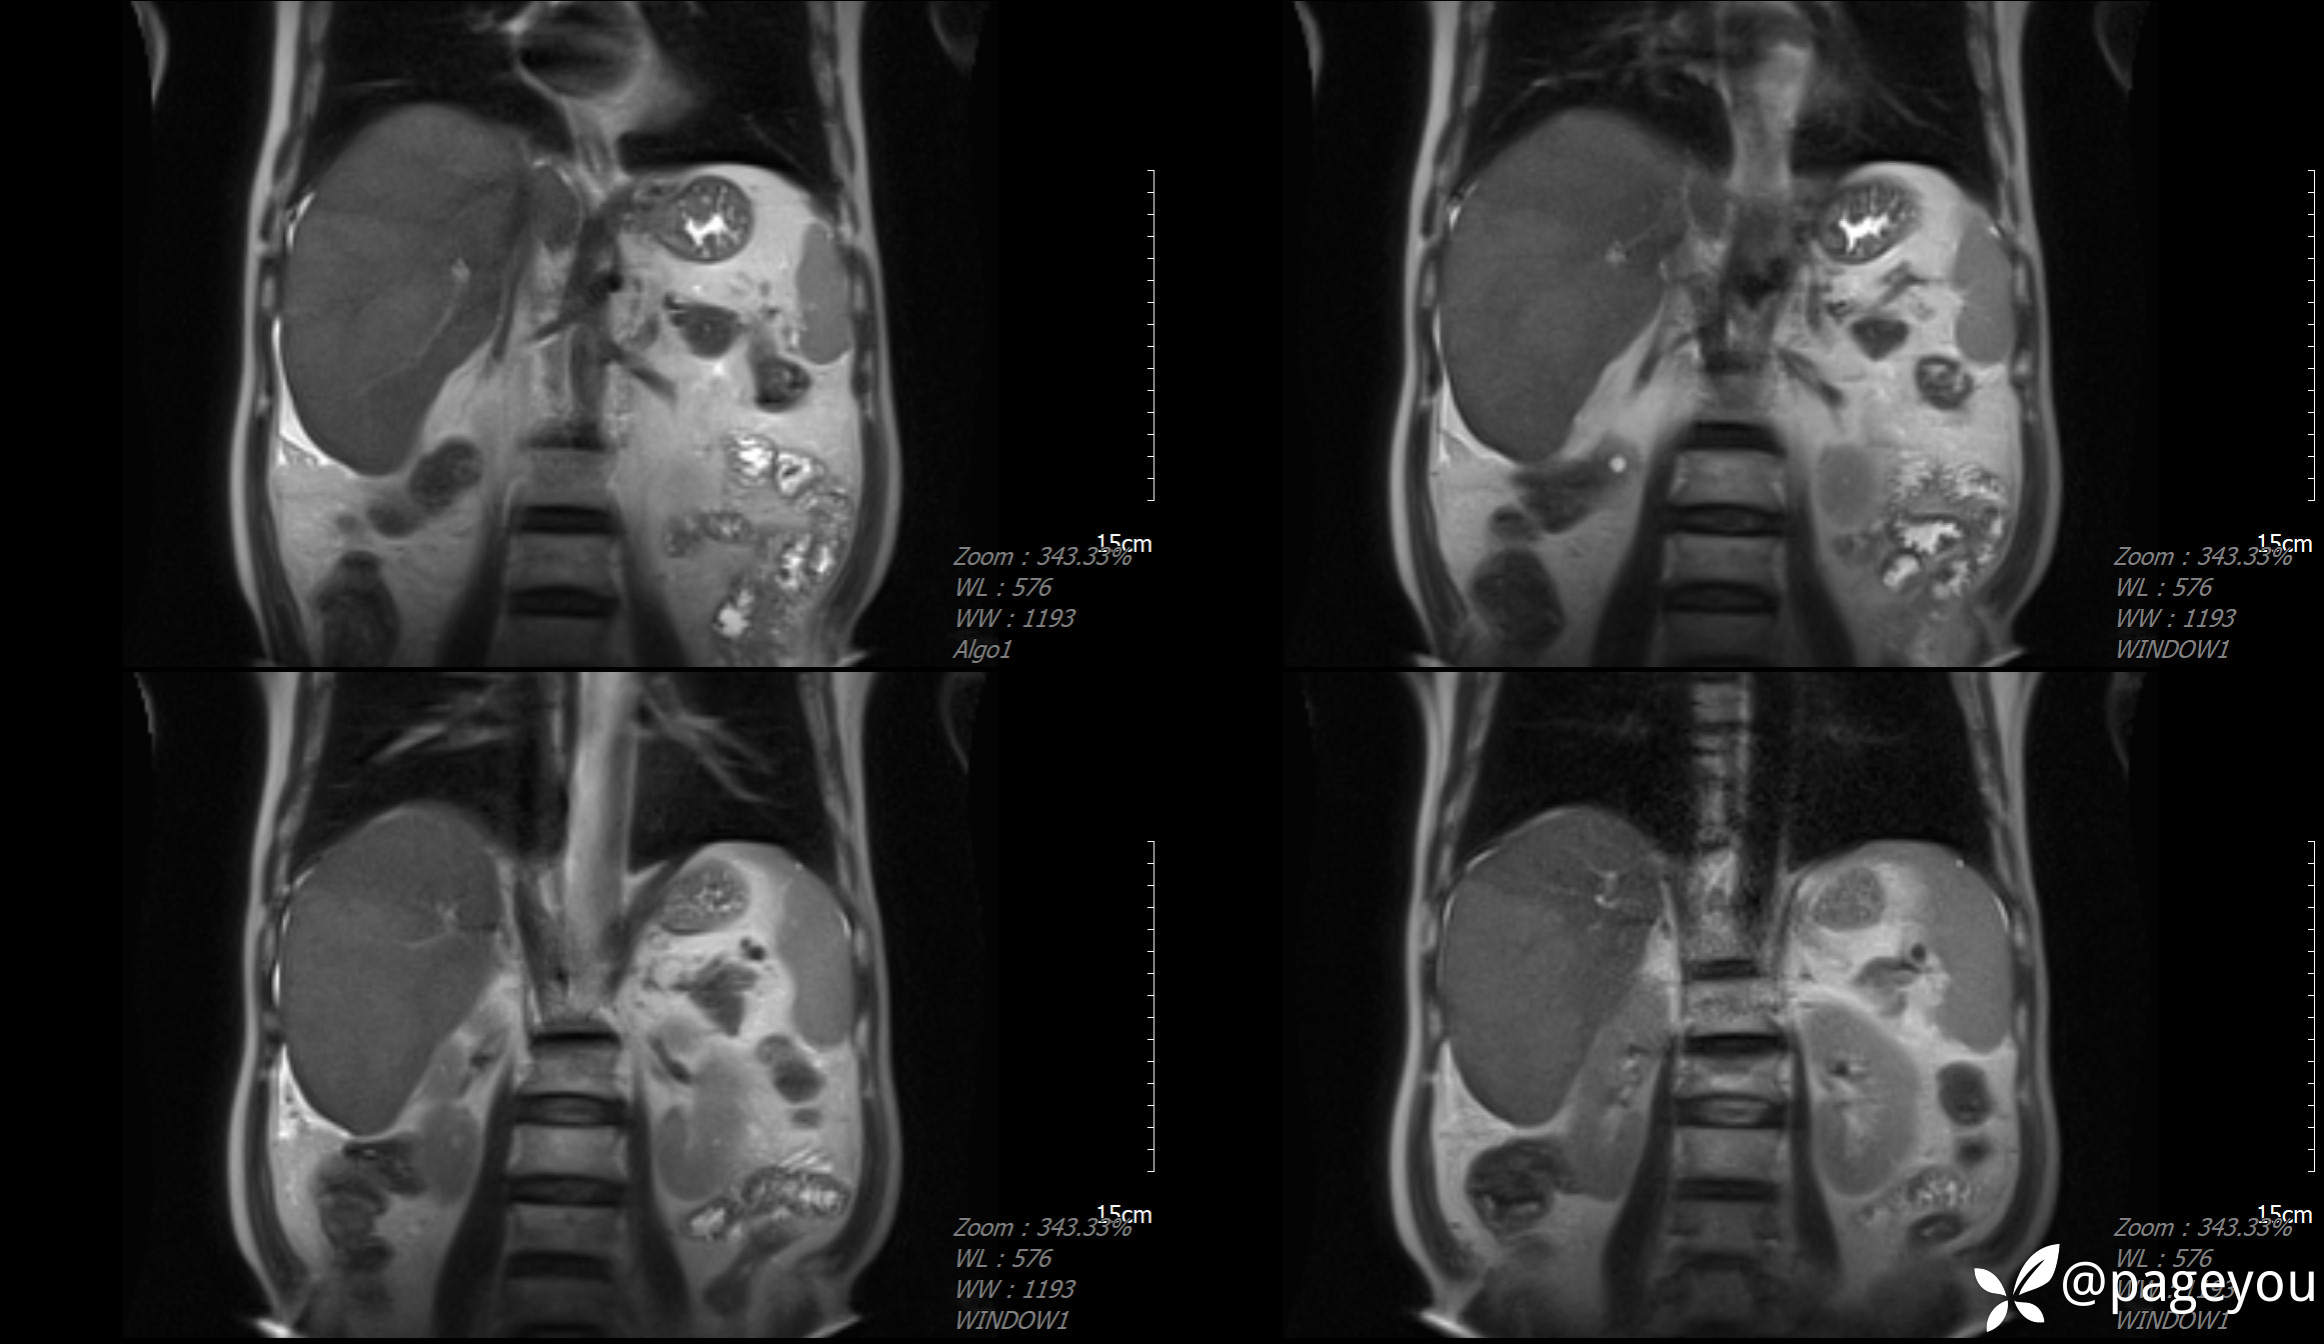

MRI检查: